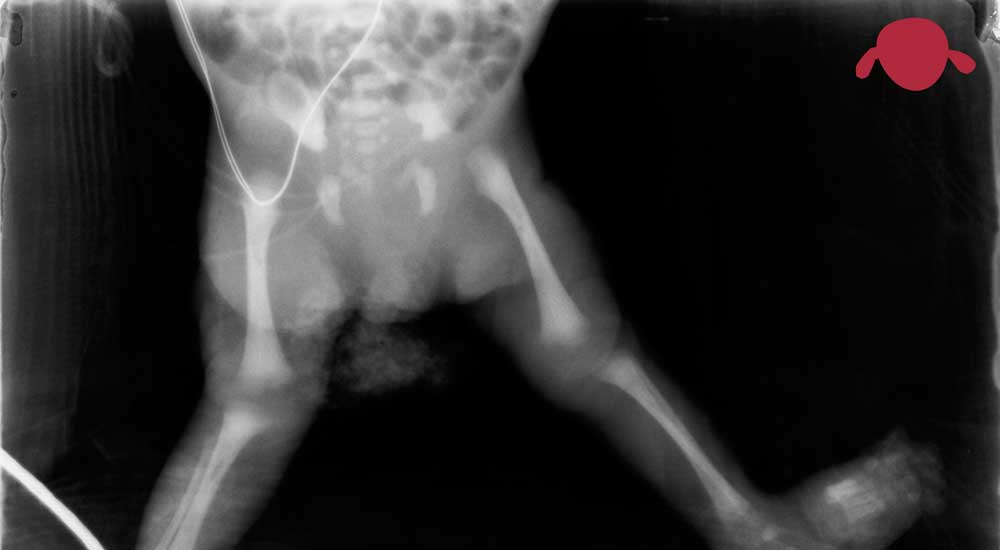

Déjenos a los Traumatólogos infantiles los problemas musculoesqueléticos de los niños. La formación propia en este campo y el conocimiento de la historia natural de las patologías servirán para orientar su caso y ofrecerle los mejores consejos.

Tengo la suerte de trabajar como Traumatólogo Infantil en Madrid, recibiendo derivaciones de casos complejos de toda España así como los casos habituales propios de nuestra población local. Esto me da la experiencia y seguridad necesaria para poder aconsejarle en los problemas musculoesqueléticos de su hijo.